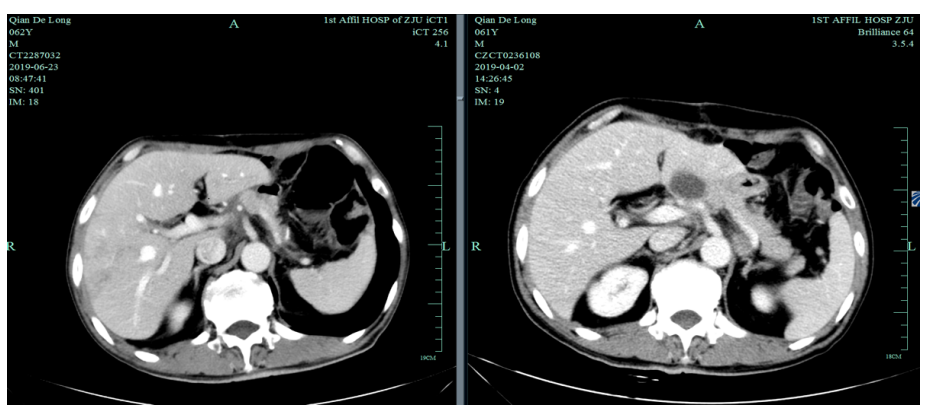

2019-4-2至2019-6-5行SOX+赫赛汀 q3w 4周期联合化疗:具体为奥沙利铂220mgD1、替吉奥3# BID D1-14、赫赛汀400mg(首次)+300mg。

由于奥沙利铂8个周期化疗结束,2019-6-26至2019-11-29行S-1+赫赛汀 q3w 8周期联合维持治疗:替吉奥3# BID D1-14、赫赛汀 300mg D1。

2019-12-20至2020-7-6行SPA+赫赛汀 q3w  8周期联合化疗:白蛋白紫杉醇250mg、替吉奥3# BID D1-14、赫赛汀 300mg D1 。

影像学评估:胃癌术后改变。持续CR。